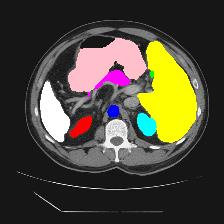

Medical image segmentation is one of the most fundamental tasks concerning medical information analysis. Various solutions have been proposed so far, including many deep learning-based techniques, such as U-Net, FC-DenseNet, etc. However, high-precision medical image segmentation remains a highly challenging task due to the existence of inherent magnification and distortion in medical images as well as the presence of lesions with similar density to normal tissues. In this paper, we propose TFCNs (Transformers for Fully Convolutional denseNets) to tackle the problem by introducing ResLinear-Transformer (RL-Transformer) and Convolutional Linear Attention Block (CLAB) to FC-DenseNet. TFCNs is not only able to utilize more latent information from the CT images for feature extraction, but also can capture and disseminate semantic features and filter non-semantic features more effectively through the CLAB module. Our experimental results show that TFCNs can achieve state-of-the-art performance with dice scores of 83.72\% on the Synapse dataset. In addition, we evaluate the robustness of TFCNs for lesion area effects on the COVID-19 public datasets. The Python code will be made publicly available on https://github.com/HUANGLIZI/TFCNs.